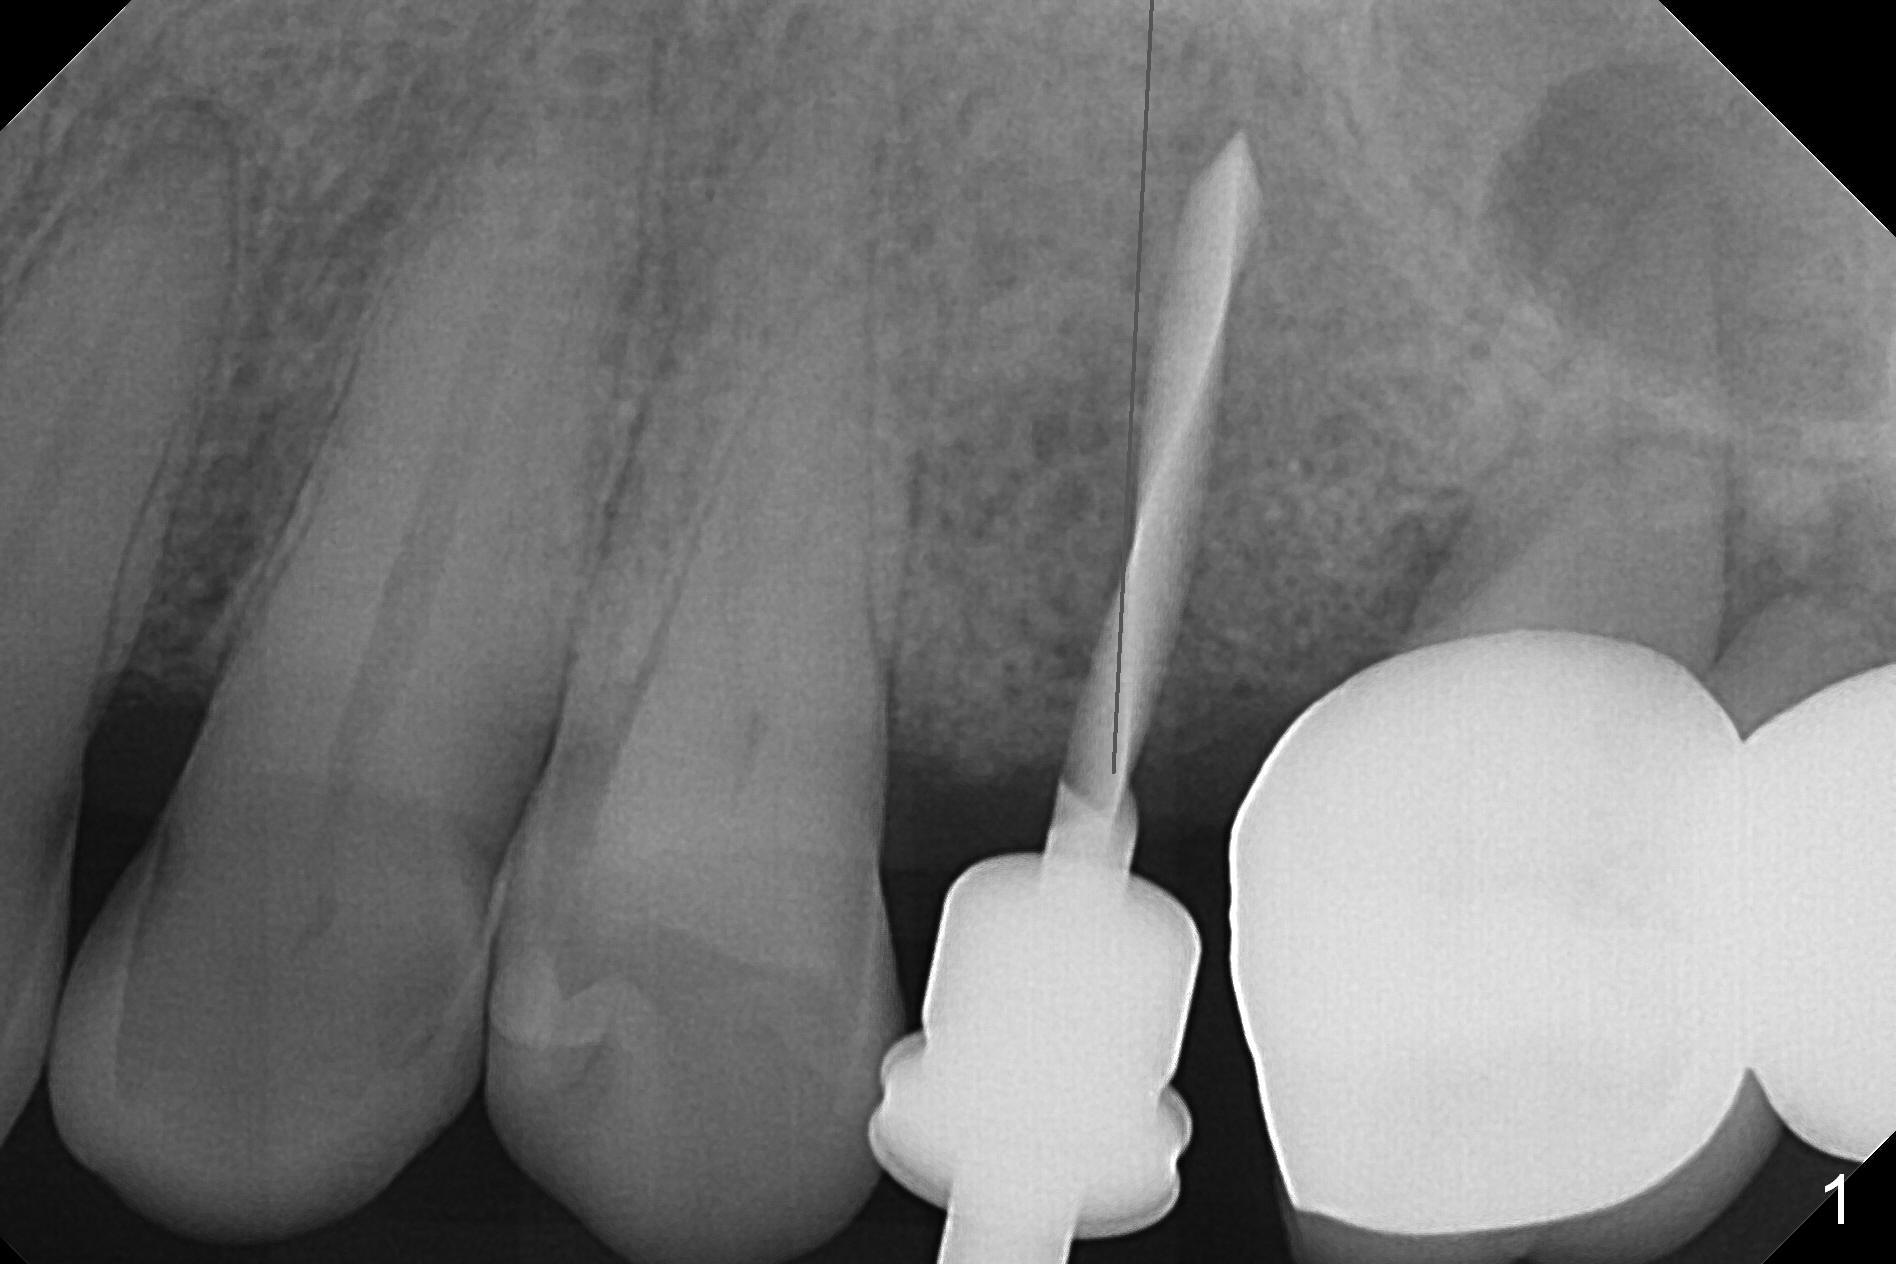

Osteotomy is initiated with Magic Split and a 1.6 mm drill at #13 before #14/15 cantilever bridge is removed (Fig.1). The trajectory is to be corrected (black line) in case an implant is placed at #14. After using Lindamann bur and reusing the 1.6 mm drill, a 3 mm Magic Expander is tapped in for 15 mm with ideal trajectory (Fig.2).